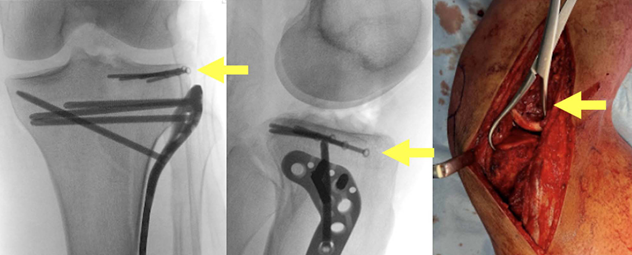

病例展示:后外侧劈裂塌陷骨折(Kfuri-Schatzker type II P型),A. 入院X线片,B. CT三维重建:清晰显示一个延长的后外侧劈裂骨块(星号标注)。此形态学分类有助于理解骨折的稳定性和手术策略。C. Carlson入路手术步骤:患者俯卧位,切口略偏内侧,与腓骨走向平行。神经显露:腓总神经(星号标注)位于浅筋膜下方、腓肠肌外侧头外侧,易于辨识。深层显露:将比目鱼肌从腓骨上剥离并抬起。将腘肌向内侧牵开。此时可显露外侧半月板(#号标注)。关节内观察:将外侧半月板向近端牵开后,可见后外侧缘的粉碎情况。

病例示例:Kfuri-Schatzker type V AL + PL + PM型双髁骨折合并后外侧“薄片型”劈裂骨折。 本例采用 Frosch入路(改良单切口双窗技术)进行处理,并应用了垂直放置的支撑钢板进行固定(箭头指示)。

图示说明:运用扩展前外侧入路处理一例Kfuri-Schatzker type II A + P型骨折。通过一个前外侧皮质骨窗(骨凿插入处),为抬升后外侧象限的塌陷关节面提供了通路(箭头所示)。水平钢板(箭头所示)实现了对后外侧象限的筏式固定,并包容了后外侧和前外侧的关节缘。

图示说明:适用于同时存在前交叉韧带和后外侧角损伤的情况。外侧副韧带和腘肌的损伤使得能够进入后外侧缘,并通过胫骨内旋来复位巨大的软骨骨折块,该骨块已在关节内剪切脱落(箭头所示)并在后外侧象限留下缺损(箭头所示)。使用钳子对骨折块进行解剖复位(箭头所示)后,采用独立螺钉进行固定(箭头所示)。使用Arciero技术实现了后外侧角重建。